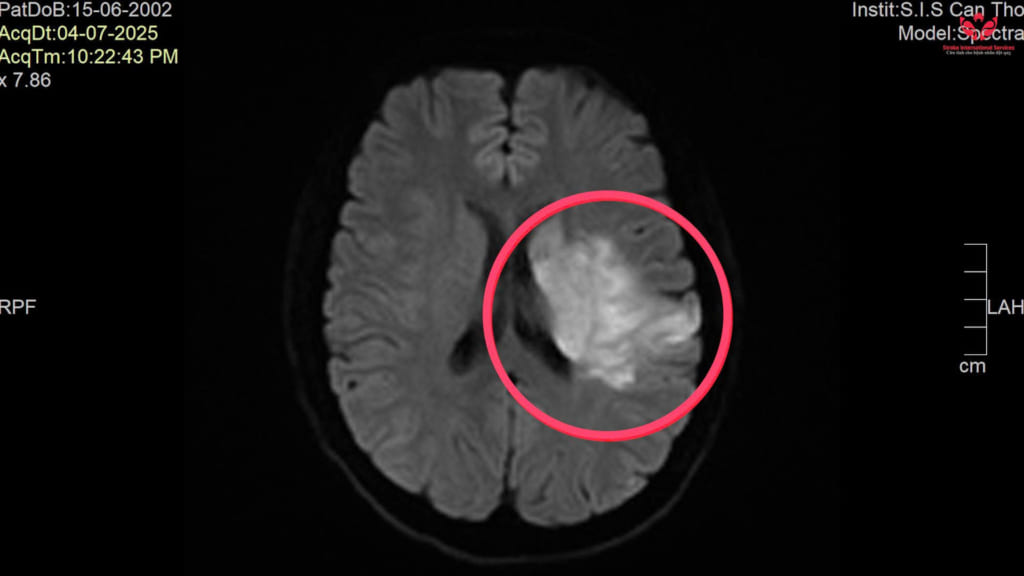

Thông tin ban đầu, bệnh nhân được người nhà phát hiện trong tình trạng lơ mơ, yếu nửa người phải và được chuyển đến Bệnh viện Đa khoa Quốc tế S.I.S Cần Thơ cấp cứu. Kết quả chụp mạch máu não tại S.I.S cho thấy bệnh nhân bị tắc động mạch cảnh trong và động mạch não giữa bên trái, dẫn đến đột quỵ nhồi máu não.

Các bác sĩ tiến hành can thiệp cấp cứu bằng phương pháp hút huyết khối cơ học, giúp tái thông hoàn toàn vùng mạch bị tắc, hạn chế tổn thương não lan rộng. Hiện bệnh nhân đang được theo dõi sát tại khu hồi sức tích cực (ICU).